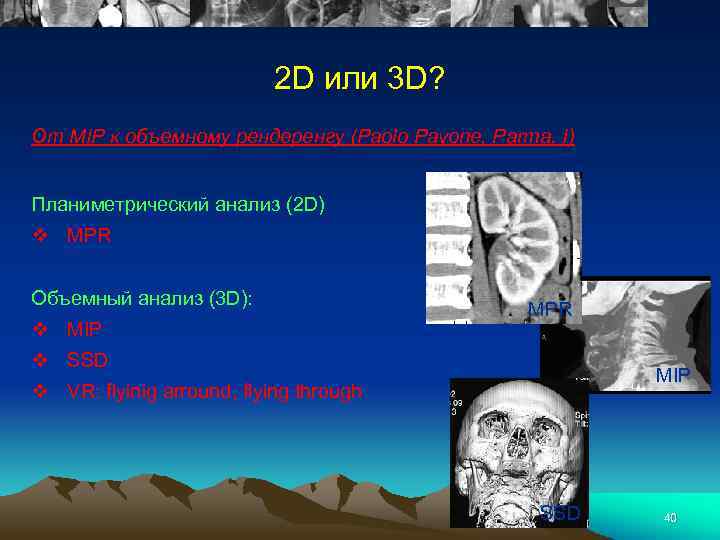

3 -ий Международный семинар по многосрезовой компьютерной томографии (МСКТ), 3 D визуализации, виртуальной эндоскопии 6 -8 июня 2002, Рим 39

2 D или 3 D? От MIP к объемному рендеренгу (Paolo Pavone, Parma, I) Планиметрический анализ (2 D) v MPR Объемный анализ (3 D): v MIP MPR v SSD MIP v VR: flyinig arround, flying through SSD 40